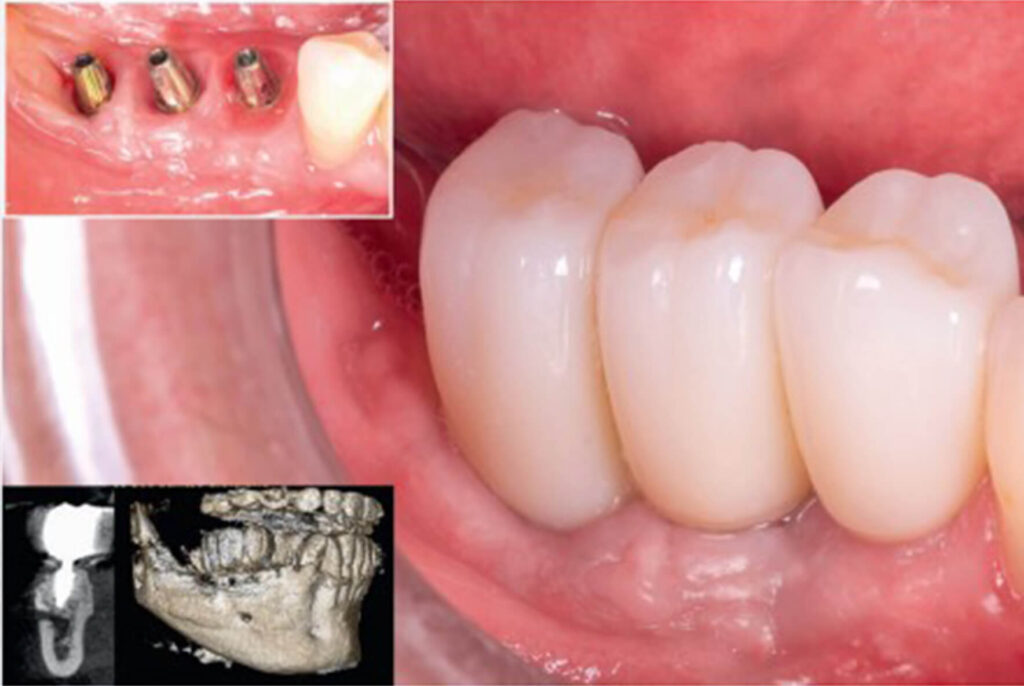

Após três meses, constatou-se a neoformação óssea adequada. Assim, foram instalados três implantes cone-morse Maestro (Implacil Osstem) com estabilidade primária satisfatória e aproximadamente 20 N·cm de torque de inserção (Fig. 8); após a instalação dos implantes, para ganho de volume tecidual e diminuição da remodelação do tecido ósseo, foi realizada a colocação de enxerto ósseo xenógeno com colágeno (Extragraft, Implacil Osstem) (Fig. 9). Três meses após a osseointegração, os implantes foram reabertos para instalação dos pilares protéticos (Ideale, Implacil Osstem) e confecção das coroas provisórias, seguidas da finalização com as cerâmicas definitivas unitárias em zircônia monolítica após mais três

meses de terapia (Figs. 9 e 10).

Figura 8: Reabertura após o período de 3 meses para a instalação de 3 implantes Maestro (Implacil Osstem) de 3,5 × 10 mm

Figura 10: Instalação de Pilares Ideale (Implacil Osstem) e provisorização após 3 meses da instalação dos implantes e finalização das cerâmicas após 6 meses. Controle de 2 anos em TCFC.